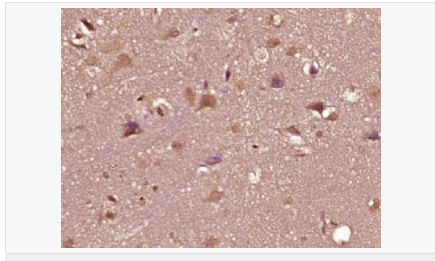

| 產(chǎn)品應(yīng)用 | WB=1:500-2000 ELISA=1:5000-10000 IHC-P=1:100-500 IHC-F=1:100-500 Flow-Cyt=1ug/Test IF=1:100-500 (石蠟切片需做抗原修復(fù)) not yet tested in other applications. optimal dilutions/concentrations should be determined by the end user. |

| 產(chǎn)品介紹 | The androgen receptor gene is more than 90 kb long and codes for a protein that has 3 major functional domains: the N-terminal domain, DNA-binding domain, and androgen-binding domain. The protein functions as a steroid-hormone activated transcription factor. Upon binding the hormone ligand, the receptor dissociates from accessory proteins, translocates into the nucleus, dimerizes, and then stimulates transcription of androgen responsive genes. This gene contains 2 polymorphic trinucleotide repeat segments that encode polyglutamine and polyglycine tracts in the N-terminal transactivation domain of its protein. Expansion of the polyglutamine tract causes spinal bulbar muscular atrophy (Kennedy disease). Mutations in this gene are also associated with complete androgen insensitivity (CAIS). Two alternatively spliced variants encoding distinct isoforms have been described. [provided by RefSeq, Jul 2008] Function: Steroid hormone receptors are ligand-activated transcription factors that regulate eukaryotic gene expression and affect cellular proliferation and differentiation in target tissues. Transcription factor activity is modulated by bound coactivator and corepressor proteins. Transcription activation is down-regulated by NR0B2. Activated, but not phosphorylated, by HIPK3 and ZIPK/DAPK3. [ENZYME REGULATION] AIM-100 (4-amino-5,6-biaryl-furo[2,3-d]pyrimidine) suppresses TNK2-mediated phosphorylation at Tyr-267. Inhibits the binding of the Tyr-267 phosphorylated form to androgen-responsive enhancers (AREs) and its transcriptional activity. Subunit: Binds DNA as a homodimer. Part of a ternary complex containing AR, EFCAB6/DJBP and PARK7. Interacts with HIPK3 and NR0B2 in the presence of androgen. The ligand binding domain interacts with KAT7/HBO1 in the presence of dihydrotestosterone. Interacts with EFCAB6/DJBP, PELP1, PQBP1, RANBP9, RBAK, SPDEF, SRA1, TGFB1I1, ZNF318 and RREB1. Interacts with ZMIZ1/ZIMP10 and ZMIZ2/ZMIP7 which both enhance its transactivation activity. Interacts with SLC30A9 and RAD54L2/ARIP4. Interacts via the ligand-binding domain with LXXLL and FXXLF motifs from NCOA1, NCOA2, NCOA3, NCOA4 and MAGEA11. The AR N-terminal poly-Gln region binds Ran resulting in enhancement of AR-mediated transactivation. Ran-binding decreases as the poly-Gln length increases. Interacts with HIP1 (via coiled coil domain). Interacts (via ligand-binding domain) with TRIM68. Interacts with TNK2. Interacts with USP26. Interacts with RNF6. Interacts (regulated by RNF6 probably through polyubiquitination) with RNF14; regulates AR transcriptional activity. Interacts with PRMT2 and TRIM24. Interacts with GNB2L1/RACK1. Interacts with RANBP10; this interaction enhances dihydrotestosterone-induced AR transcriptional activity. Interacts with PRPF6 in a hormone-independent way; this interaction enhances dihydrotestosterone-induced AR transcriptional activity. Interacts with STK4/MST1. Interacts with ZIPK/DAPK3. Interacts with LPXN. Interacts with MAK. Part of a complex containing AR, MAK and NCOA3. Subcellular Location: Nucleus. Cytoplasm. Note=Predominantly cytoplasmic in unligated form but translocates to the nucleus upon ligand-binding. Can also translocate to the nucleus in unligated form in the presence of GNB2L1. Tissue Specificity: Isoform 2 is mainly expressed in heart and skeletal muscle. Post-translational modifications: Sumoylated on Lys-386 (major) and Lys-520. Ubiquitinated. Deubiquitinated by USP26. 'Lys-6' and 'Lys-27'-linked polyubiquitination by RNF6 modulates AR transcriptional activity and specificity. Phosphorylated in prostate cancer cells in response to several growth factors including EGF. Phosphorylation is induced by c-Src kinase (CSK). Tyr-534 is one of the major phosphorylation sites and an increase in phosphorylation and Src kinase activity is associated with prostate cancer progression. Phosphorylation by TNK2 enhances the DNA-binding and transcriptional activity and may be responsible for androgen-independent progression of prostate cancer. Phosphorylation at Ser-81 by CDK9 regulates AR promoter selectivity and cell growth. Phosphorylation by PAK6 leads to AR-mediated transcription inhibition. Palmitoylated by ZDHHC7 and ZDHHC21. Palmitoylation is required for plasma membrane targeting and for rapid intracellular signaling via ERK and AKT kinases and cAMP generation. DISEASE: Defects in AR are the cause of androgen insensitivity syndrome (AIS) [MIM:300068]; previously known as testicular feminization syndrome (TFM). AIS is an X-linked recessive form of pseudohermaphroditism due end-organ resistance to androgen. Affected males have female external genitalia, female breast development, blind vagina, absent uterus and female adnexa, and abdominal or inguinal testes, despite a normal 46,XY karyotype. Defects in AR are the cause of spinal and bulbar muscular atrophy X-linked type 1 (SMAX1) [MIM:313200]; also known as Kennedy disease. SMAX1 is an X-linked recessive form of spinal muscular atrophy. Spinal muscular atrophy refers to a group of neuromuscular disorders characterized by degeneration of the anterior horn cells of the spinal cord, leading to symmetrical muscle weakness and atrophy. SMAX1 occurs only in men. Age at onset is usually in the third to fifth decade of life, but earlier involvement has been reported. It is characterized by slowly progressive limb and bulbar muscle weakness with fasciculations, muscle atrophy, and gynecomastia. The disorder is clinically similar to classic forms of autosomal spinal muscular atrophy. Note=Caused by trinucleotide CAG repeat expansion. In SMAX1 patients the number of Gln ranges from 38 to 62. Longer expansions result in earlier onset and more severe clinical manifestations of the disease. Note=Defects in AR may play a role in metastatic prostate cancer. The mutated receptor stimulates prostate growth and metastases development despite of androgen ablation. This treatment can reduce primary and metastatic lesions probably by inducing apoptosis of tumor cells when they express the wild-type receptor. Defects in AR are the cause of androgen insensitivity syndrome partial (PAIS) [MIM:312300]; also known as Reifenstein syndrome. PAIS is characterized by hypospadias, hypogonadism, gynecomastia, genital ambiguity, normal XY karyotype, and a pedigree pattern consistent with X-linked recessive inheritance. Some patients present azoospermia or severe oligospermia without other clinical manifestations. Similarity: Belongs to the nuclear hormone receptor family. NR3 subfamily. Contains 1 nuclear receptor DNA-binding domain. SWISS: P10275 Gene ID: 367 Database links: Entrez Gene: 367 Human Entrez Gene: 11835 Mouse Omim: 313700 Human SwissProt: P10275 Human SwissProt: P19091 Mouse Unigene: 496240 Human Unigene: 39005 Mouse Unigene: 394224 Mouse Unigene: 439657 Mouse Unigene: 9813 Rat Important Note: This product as supplied is intended for research use only, not for use in human, therapeutic or diagnostic applications. AR是一個(gè)由917個(gè)氨基酸組成的蛋白質(zhì),位于雄激素靶組織細(xì)胞中或細(xì)胞表面上的特異分子部位或結(jié)構(gòu)。 AR在前列腺癌中起著重要的作用,研究表明AR的表達(dá)與組織分型形成一定的相關(guān)性 ,AR在高分化的腫瘤中表達(dá)較多,而在低分化的腫瘤中表達(dá)較少。用于前列腺癌的檢測,指導(dǎo)臨床治療,目前可用于乳腺癌、食道癌等各項(xiàng)腫瘤的研究。 |